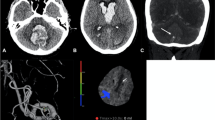

To focus on cerebral hemodynamics instead of only angiographic vasospasm, CT perfusion imaging can be applied for detection and even prediction of DCI and may be especially useful in aSAH patients who are neurologically not assessable, but previous studies reported conflicting results in this respect [18]. For treatment of patients with clinical or radiological features of DCI, hypertension often is induced to ameliorate neurological worsening and prevent cerebral infarction and poor neurological outcomes [9, 16]. In patients with DCI refractory to induce hypertension, additional rescue therapy strategies, such as intra-arterial administration of nimodipine, are often considered [5, 7]. However, such treatments carry a risk of major complications and their risk–benefit ratio remains uncertain. We aimed to determine the effect of implementing a multidisciplinary approach, with frequent and standardized clinical assessment, standardized monitoring with CT perfusion, and a medical instead of an invasive initial step in the treatment of DCI on radiologically proven infarction and functional outcome in patients with aSAH.

Radiological DCI was defined as a 1.5-fold prolongation of mean transit time (MTT) values, compared to baseline in serial CT perfusion imaging [3]. Severe angiographic vasospasm was defined as narrowing of the arterial diameter of > 70% from the baseline on digital subtraction angiography.

In fall 2015, the authors (NE, CG, ENP, JK) developed and implemented an interdisciplinary protocol for standardized detection and management of DCI (see below) in line with their previously reported studies [6, 10]. Following a transition period, from January 2016 onward, all aSAH patients admitted to our department (post-implementation cohort) were routinely discussed in a multidisciplinary team of neurosurgeons, neuroradiologists, and intensive care specialists, and management decisions in case of deterioration were taken based on the protocol and multidisciplinary discussion. The standardized detection protocol included thorough neurological examinations every 2–4 h by dedicated neurocritical care residents in combination with a novel CT perfusion screening protocol (Fig. 1). CT perfusion measurements were performed 6–12 h after aneurysm treatment, on days 3 or 4 as well as days 9 to 11 after aSAH, or in case of clinical features of DCI [6, 10, 17]. For patients who were and remained in perfect condition, the last CT perfusion was omitted. Additionally, digital subtraction angiographies were performed on admission and on days 6 to 9 after aSAH ictus and in case of clinical deterioration from DCI or CT perfusion deficits. In the case of persistent clinical signs of DCI, severe CT perfusion impairment or severe angiographic vasospasm, the patients in the post-implementation cohort were treated by means of a standardized, escalating treatment protocol: First, induced hypertension with a targeted systolic blood pressure of > 180 mmHg; second, solitary intra-arterial nimodipine bolus applications during catheter angiography; and third angiographic application of an intra-arterial catheter for continuous nimodipine administration over 48 h with CT perfusion imaging in between each escalating step (Fig. 2b).

Any cerebral infarction occurred in 67 (46.9%) patients in the pre-implementation cohort and in 46 (29.1%) in the post-implementation cohort (aOR: 0.41 [0.24–0.69]). DCI-related cerebral infarction occurred in 45 (31.5%) patients in the pre-implementation cohort and in 28 (17.7%) patients in the post-implementation cohort, aOR was 0.41 [0.23–0.76] (Table 2, Figs. 3 and 5).